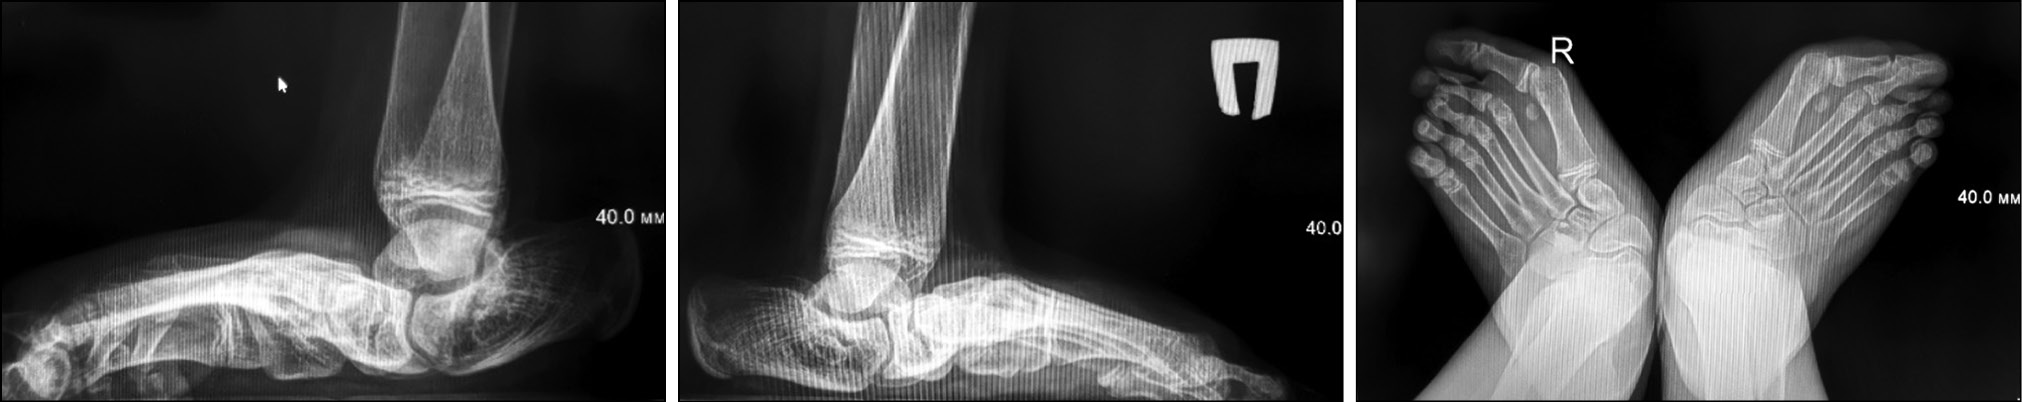

На боковой рентгенограмме с максимальной подошвенной флексией проявится стойкое смещение длинника таранной кости и первой плюсневой кости (рис. 4), причем значения базового угла между осями этих костей более 35° считаются диагностическими для вертикальной таранной кости [35]. Тем не менее вертикальный таран не может быть исключен со значениями угла менее 35°. В таких случаях наличие или отсутствие эквинуса должно быть зафиксировано. Если эквинус присутствует, то деформация считается жесткой и требует лечения таким же образом, как и для вертикального тарана с углом более 35°. В отличие от этого, при подошвенном сгибании боковая рентгенография косой таранной кости продемонстрирует восстановление нормального соотношения между длинной осью таранной кости и первой плюсневой костью [1] (рис. 4).

Рис. 4. Пациент С., 2 года. Боковая рентгенограмма с максимальной подошвенной флексией. Врожденный вертикальный таран справа, косой таран слева

Fig. 4. Patient S., 2 years old. Lateral radiograph with maximum plantar flexion. Congenital vertical talus on the right, oblique talus on the left

На боковой рентгенограмме с максимальной тыльной флексией (рис. 5) наблюдается стойкое увеличение большеберцово-пяточного угла относительно нормальных значений, что указывает на фиксированный эквинус.

Рис. 5. Пациент С., 2 года. Боковая рентгенограмма с максимальной тыльной флексией. Врожденный вертикальный таран справа, косой таран слева

Fig. 5. Patient S., 2 years old. Lateral radiograph with maximum dorsiflexion. Congenital vertical talus on the right, oblique talus on the left